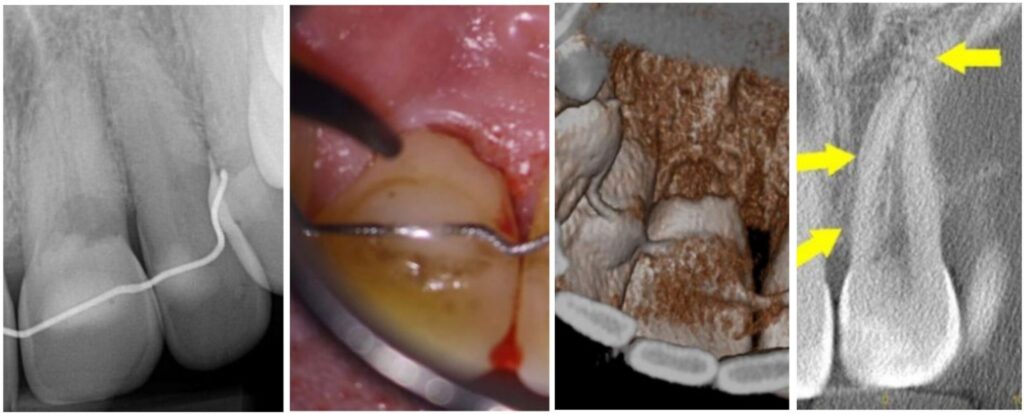

• Cervical resorption (hides right by the gumline, throws on a disguise and pretends to be decay—sneaky little punk)

Cervical resortion: Note the apical extensions and circumpulpal spread